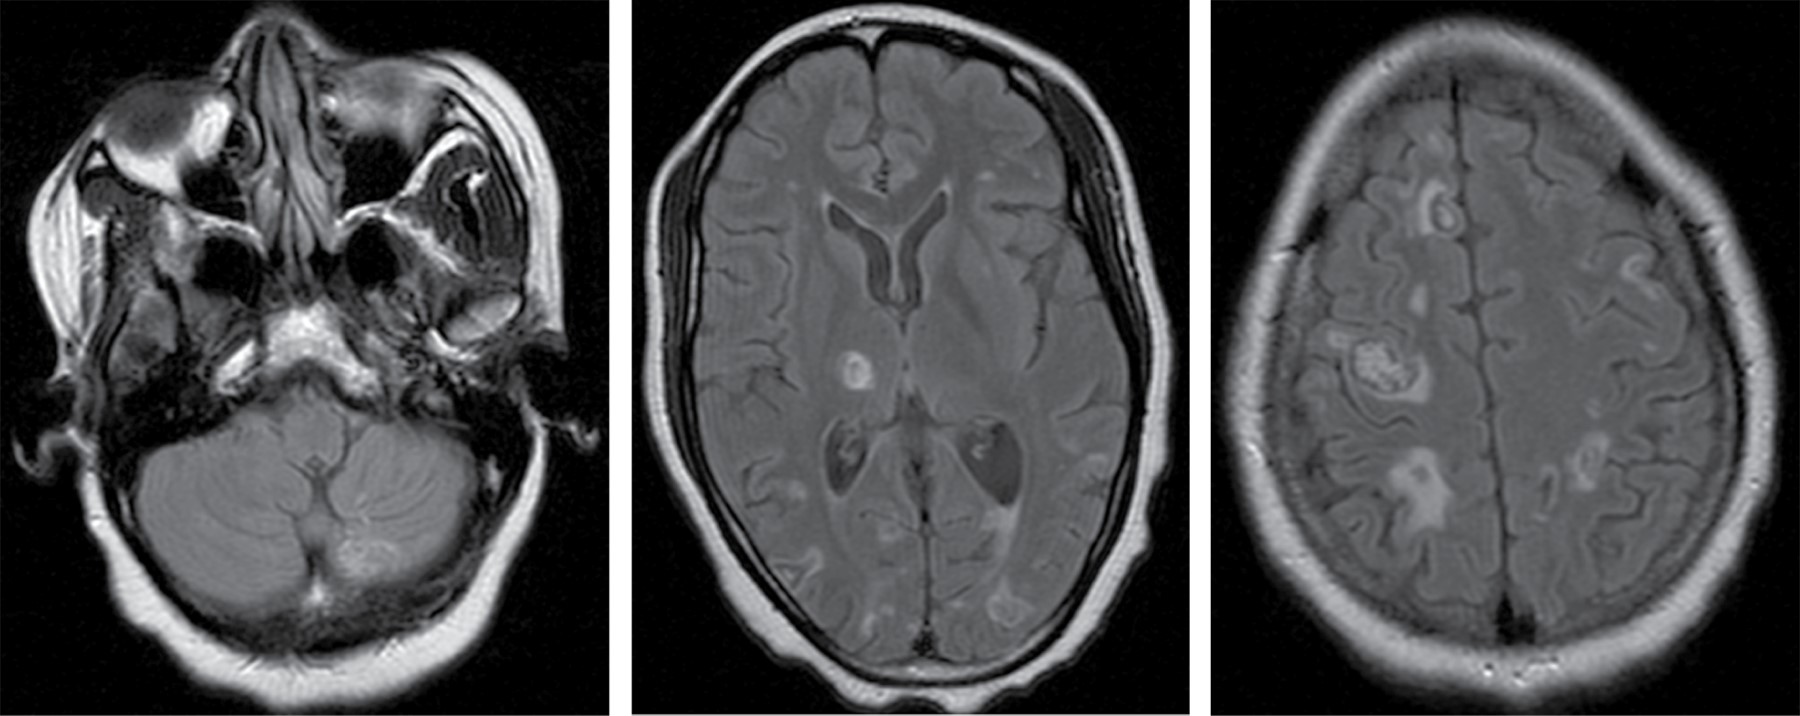

Durante el ingreso, el paciente no mejoró neurológicamente, por lo que se realizó una RM (resonancia magnética) cerebral, que mostró múltiples lesiones anulares que afectaban a ambos hemisferios cerebelosos, mesencéfalo, tálamo y ganglios basales. Estas lesiones presentaron un predominio central hipointenso en secuencias ponderadas en T1 e hiperintensidad en T2 y FLAIR (Figura 2).

Estos hallazgos fueron altamente sugestivos de toxoplasmosis cerebral con afectación supra e infratentorial a nivel talámico y protuberancial. Tras la sospecha diagnóstica, se determinaron IgG específicas para Toxoplasma spp. que fueron positivas con un título de 420.7 U/mL.

En los últimos años, se ha utilizado la resonancia magnética nuclear (RMN) con espectroscopia donde se describe un patrón inflamatorio, con un aplanamiento en el nivel de captación de N-acetil aspartato (NAA), un pequeño aumento de colina (Ch) y un pico de lípidos y lactato.